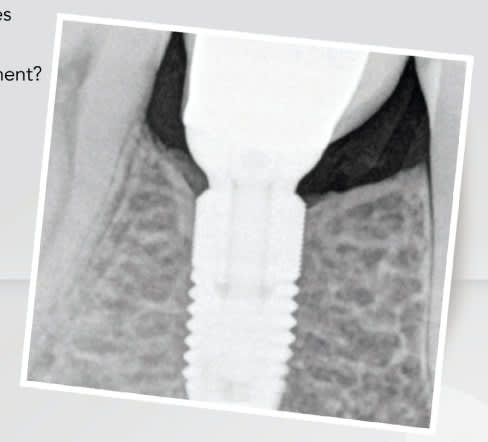

fric fric fric !

l'étude de cas et les guides chir au départ rendent l'implantologie peu rentable apparemment